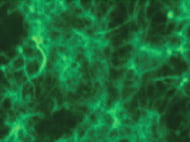

Mesenchymal stem cells, also commonly known as mesenchymal stromal cells obtained from bone marrow are multipotent cells with the ability to differentiate into cells of various mesenchyme origins....

Mesenchymal Stem Cells derived from adipose tissue have immense regenrative potential. They are responsible for replacing damaged tissue and maintaining an extracellular matrix. They are used for toxiticity...

Mesenchymal Stem Cells derived from adipose tissue have immense regenerative potential. They are responsible for replacing damaged tissue and maintaining an extracellular matrix. They are used for toxicity...